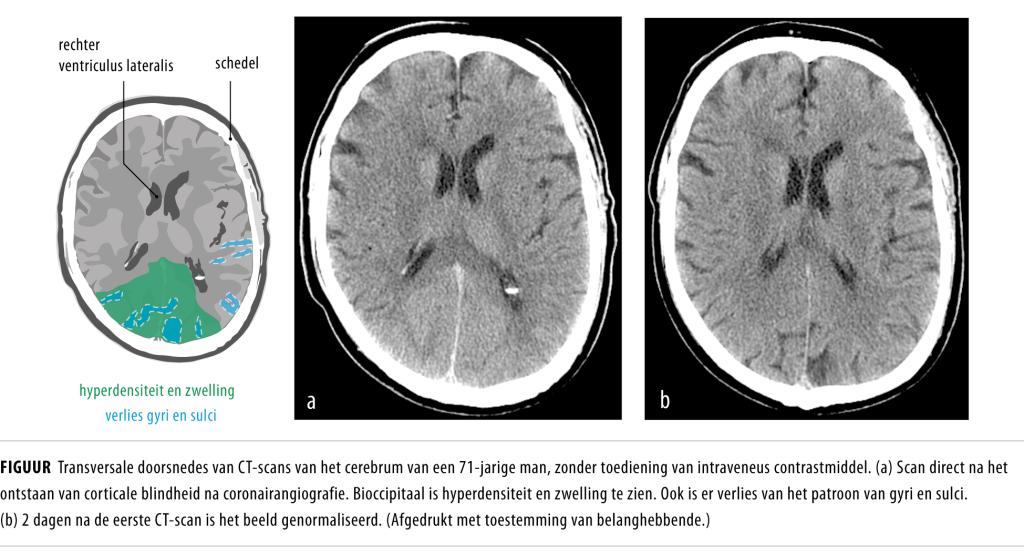

Wij werden in consult geroepen bij een 71-jarige man met progressief visusverlies, hoofdpijn, misselijkheid en braken. De symptomen waren ontstaan direct na coronairangiografie vanwege typische thoracale pijn. In het verleden had patiënt een acuut myocardinfarct gehad, waarvoor hij was behandeld met een percutane coronaire interventie. Op het huidige coronairangiogram was een occlusie te zien van de ‘graft’ van de ramus interventricularis posterior (ramus descendens posterior, RDP). Tijdens de angiografie was de bloeddruk niet-afwijkend gebleven en werd gebruikgemaakt van jodixanol, een non-ionisch, jodiumhoudend contrastmiddel. Bij neurologisch onderzoek van patiënt constateerden we corticale blindheid. Een CT-scan van het cerebrum toonde bioccipitaal…